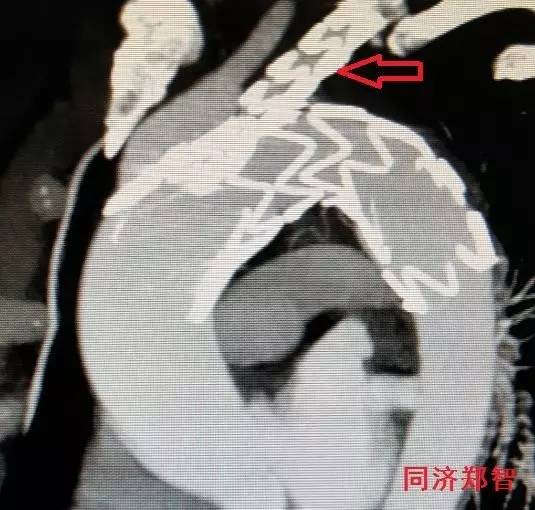

主动脉穿透性溃疡有时候很小,不易发现,需要明察秋毫。图9显示CTA三维重建中胸降主动脉起始部位小溃疡形成(红箭头所示)。

图9